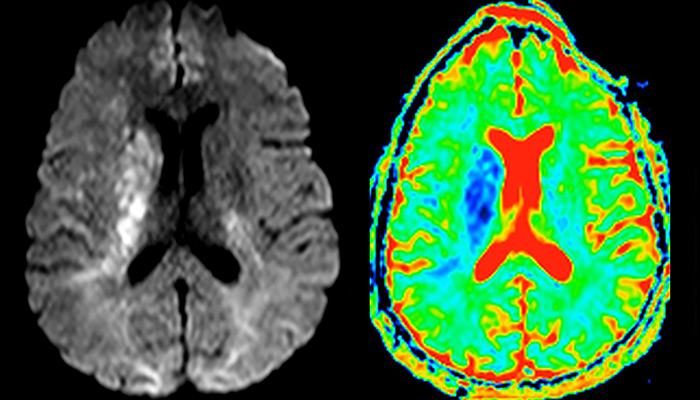

“Every center is different, but for me the ideal protocol for stroke includes diffusion weighted imaging, FLAIR, and fast susceptibility imaging,” says Dr. Savatovsky. “Our fast susceptibility weighted imaging takes 50 seconds, so it’s as fast as T2*-weighted imaging. It visualizes hemorrhage but also the clots. We also do 3D MR angiography that provides information on cervical and brain vessels. If the patient does not need immediate treatment, or if additional information is needed to decide on treatment, we might also add perfusion imaging and post-contrast T1-weighted imaging.”